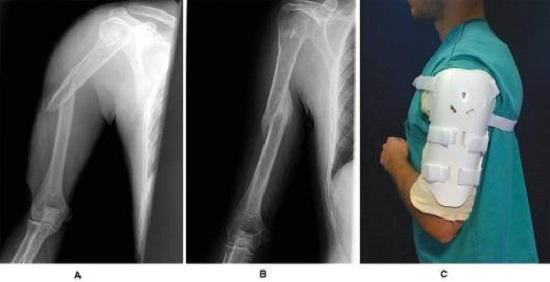

肱骨即上臂骨,其上端;通过肱骨头与肩关节相连,下端通过肱骨髁与肘关节相连。所谓肱骨干骨折,是指肱骨头和肱骨髁以外的肱骨主干部分骨折。根据骨折类型的不同,可将肱骨干骨折分为横形骨折、斜行骨折、螺旋形骨折和粉碎型骨折等类型,如果是不稳定的横形骨折和粉碎型骨折,或者伴有重要神经和血管损伤(肱骨上附有诸多肌肉,骨折后常常因为肌肉张力使骨折移位、成角增大,使贴近肱骨的血管和神经受损),就必须要采用切开、复位、固定、修复的手段进行手术治疗,并在术后参考如下方案进行康复治疗。